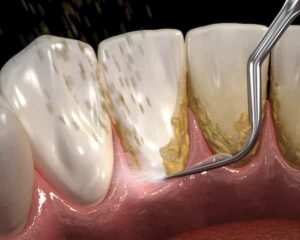

Manual Scaling with Hand Curettes

- Manual Scaling with Hand Curettes: We rarely use these sharp, hand-held tools, and only after ultrasonic or sonic scaling if needed for fine-tuning. They involve scraping by hand to remove stubborn spots.

- Pros: They give precise control in hard-to-reach areas and can be very effective for detailed work.

- Cons: Because they’re sharp, they can remove a small amount of the tooth’s protective root cement layer if overused, which might lead to sensitivity or minor damage over time. That’s why we limit them—they’re not our first choice for a natural approach.